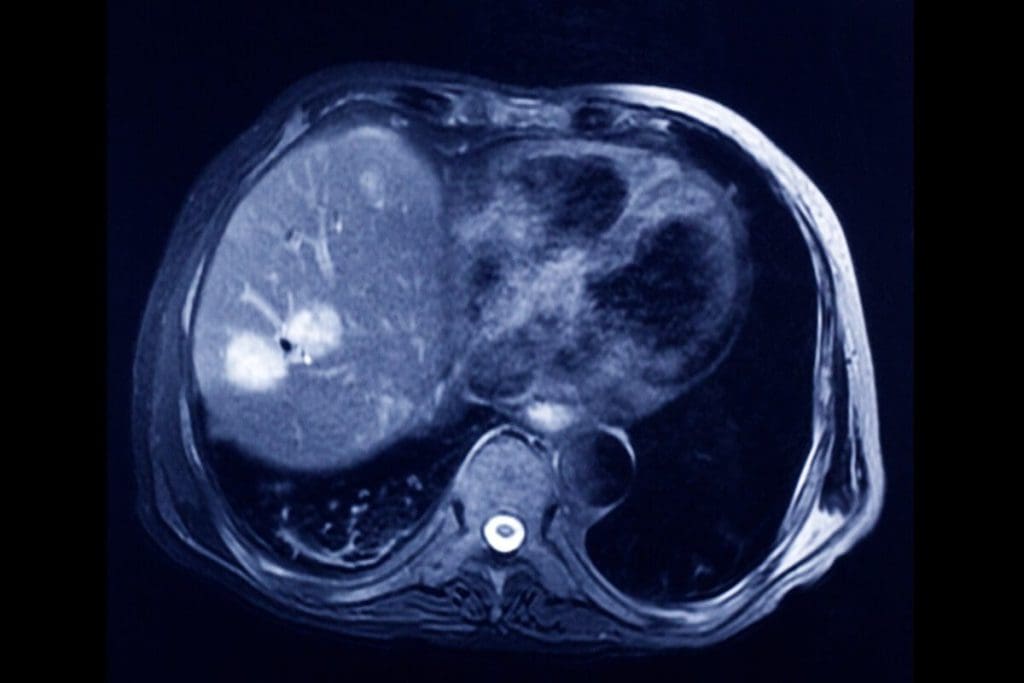

A CT urogram is a common test for the urinary system that uses a CT scan and dye to visualize the kidneys, bladder, and ureters. However, for people at low risk, safer and cheaper alternatives like renal and bladder ultrasound, contrast-enhanced ultrasound, and voiding urosonography are effective options to diagnose urinary problems without requiring a CT scan. For those wondering, does a CT scan detect tumors? The answer is yes”CT scans are highly effective at identifying many types of tumors with good accuracy, although some small or low-grade tumors might be missed. While MRI generally offers higher sensitivity and specificity, CT remains a valuable and accessible tool for tumor detection.

A CT urogram uses a CT scanner to image the kidneys, ureters, and bladder. A contrast dye is given to make the urinary tract stand out. This helps find tumors, stones, and blockages.

One big drawback of a CT urogram is the radiation exposure. Though the radiation is controlled, it can slightly raise the risk of cancer later. Patients often ask, “does a CT scan detect tumors? Yes, it can ” but weighing the risks and benefits is important.

Doctors consider safer options when possible, especially if frequent imaging is expected. Still, the ability of CT to detect tumors is one reason it’s often chosen in high-risk cases. When evaluating bladder or kidney issues, many wonder, “does a CT scan detect tumors better than other scans?” In many scenarios, it does.

Other methods like ultrasound or MRI might be better for such patients. However, when accuracy is key, does a CT scan detect tumors missed by ultrasound? Often, it does. For those with high-risk symptoms, doctors rely on CT’s precision.